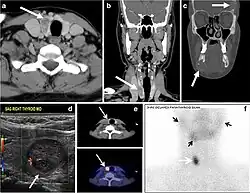

Fig. 11. Thyroid non-Hodgkin's large B-cell lymphoma in a 66-year-old female patient. an Axial enhanced neck CT scan demonstrates left thyroid lobe and isthmus homogeneously hypodense and minimally enhancing mass (white arrows). This lesion invades the prevertebral muscles (black arrows). Note the multiple enlarged level V lymph nodes (white arrowheads). b Post-treatment image shows significant reduction in size and mass effect of the left thyroid infiltrative mass, with almost complete resolution of the left cervical lymphadenopathy.[1] -

Fig. 12. Diffuse thyroid large B-cell lymphoma in a 79-year-old female patient. an Axial enhanced neck CT scan demonstrates a homogeneously hypodense and minimally enhancing large right thyroid solid mass (long white arrow) extending into the thyroid isthmus. It is encasing the right carotid artery (short white arrow) and displacing of the trachea and oesophagus to the left side.[1]

Parathyroid adenoma (PA) is the most common cause of primary hyperparathyroidism. Ectopic parathyroid adenoma is rare. The third and fourth pharyngeal pouches represent the embryological origin of the parathyroid tissues, and ectopic parathyroid adenoma can ultimately develop anywhere along their migration course. In a large retrospective study of patients with primary hyperparathyroidism, PA was detected in the intra-thyroid location in 0.7% of cases. In another retrospective analysis of 202 patients with ectopic PA, the intra-thyroidal location was found in 18% of the cases. Intra-thyroid parathyroid adenomas mimic thyroid nodules in CT scans and may even show uptake on a thyroid iodine scan. Correlation with laboratory workup, including measurement of serum parathyroid hormone and calcium level, is required. In addition, the evaluating radiologist should search for radiological manifestations of hyperparathyroidism, such as osteopenia, bone resorption, and brown tumours (Fig. 22).[1]

In the case of inconclusive Tc99m Sestamibi and neck US imaging, FNA biopsy with FNA-iPTH (intact parathyroid hormone) measurement can provide simultaneous biochemical and cytological evidence. Elevated FNA-iPTH measurement, as compared to serum iPTH, is considered positive and diagnostic of parathyroid adenoma.[1]